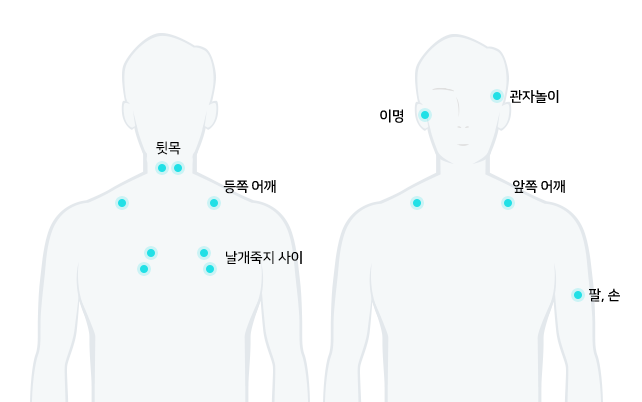

뒷목이 뻣뻣하고 목의 움직임이 제한되며, 두통, 어깨, 팔, 손까지 통증이 나타날 수 있습니다.

뒷목, 어깨 통증, 두통, 눈의 피로, 손발 저림, 이명

위 증상 중 한가지라도 해당된다면 “목 디스크”일 수 있습니다.